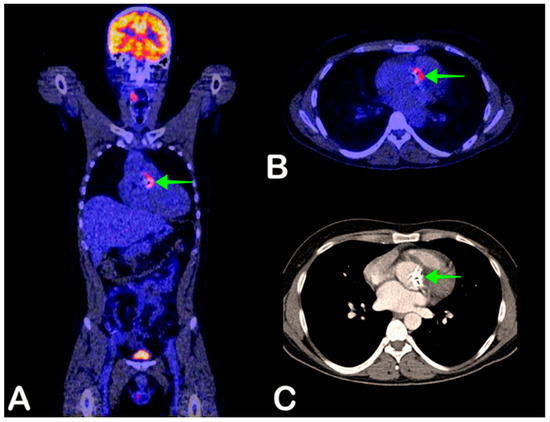

- Chen, W.; Dilsizian, V. FDG PET/CT for the diagnosis and management of infective endocarditis: Expert consensus vs evidence-based practice. J. Nucl. Cardiol. 2018, 26, 313–315. [Google Scholar] [CrossRef]

- Gomes, A.; Glaudemans, A.W.J.M.; Touw, D.J.; Van Melle, J.P.; Willems, T.P.; Maass, A.H.; Natour, E.; Prakken, N.H.J.; Borra, R.J.H.; Van Geel, P.P.; et al. Diagnostic value of imaging in infective endocarditis: A systematic review. Lancet Infect. Dis. 2017, 17, e1–e14. [Google Scholar] [CrossRef]

- Habib, G.; Lancellotti, P.; Antunes, M.J.; Bongiorni, M.G.; Casalta, J.-P.; Del Zotti, F.; Dulgheru, R.; El Khoury, G.; Erba, P.A.; Iung, B.; et al. 2015 ESC Guidelines for the management of infective endocarditis. The Task Force for the Management of Infective Endocarditis of the European Society of Cardiology (ESC). Endorsed by: European Association for Cardio-Thoracic Surgery (EACTS), the European Association of Nuclear Medicine (EANM). G. Ital. Cardiol. Rome 2016, 17, 3075–3128. [Google Scholar]

- Erba, P.A.; Pizzi, M.N.; Roque, A.; Salaun, E.; Lancellotti, P.; Tornos, P.; Habib, G. Multimodality Imaging in Infective Endocarditis. Circulation 2019, 140, 1753–1765. [Google Scholar] [CrossRef] [PubMed]